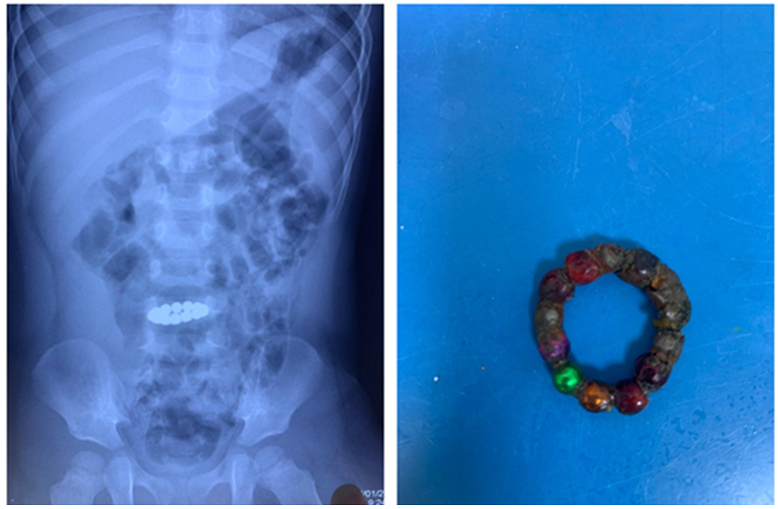

Các viên nam châm trẻ nuốt phải Ảnh: BVCC

BSCKII Nguyễn Minh Tiến - phó giám đốc Bệnh viện Nhi đồng thành phố (TP HCM) cho biết bệnh viện vừa cứu sống bé trai L.T.Q. (26 tháng tuổi, ngụ tỉnh Đồng Tháp) bị thủng tắc ruột do nuốt 14 viên nam châm gỉ sét.

Người nhà phát hiện và đưa bé đến cơ sở y tế địa phương chụp X-quang bụng. Kết quả hiển thị dị vật đang ở ruột non nên bác sĩ cho bé uống thuốc xổ và theo dõi phân của trẻ. Người nhà theo dõi thấy bé đi cầu bình thường nhưng không biết các viên bi đã ra hết chưa.

Tuy nhiên sau đó bé lại khó chịu, đau bụng, nôn nên người nhà đưa đến Bệnh viện Nhi đồng thành phố. Bác sĩ chụp X-quang bụng, phát hiện dị vật còn ở ruột non.

Một cuộc hội chẩn đã diễn ra giữa các bác sĩ chuyên khoa tiêu hóa với bác sĩ ngoại khoa. Bé nhanh chóng được nội soi đường tiêu hóa cấp cứu và nội soi ổ bụng, ghi nhận dị vật nằm ở đoạn đầu hỗng tràng, gây gập góc đoạn hỗng tràng thành một vòng viêm dính, thủng bít, thành hóa.

Các bác sĩ ngoại khoa quyết định cắt bỏ đoạn ruột viêm dính gập góc (khoảng 7cm) và nối ruột. Kết quả một tuần sau mổ, bé hết đau bụng, hết ói, tỉnh táo, tập ăn đường miệng, tiêu phân vàng.

14 viên bi nam châm với màu sắc khác nhau đều đã được lấy ra. Một số viên bi gỉ sét gây tổn thương ruột nghiêm trọng. Bé được tiếp tục theo dõi tổn thương niêm mạc ruột, chức năng đường tiêu hóa.